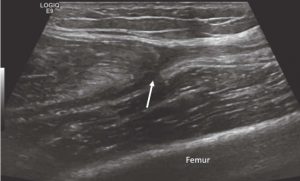

Rectus Femoris

Full-thickness tearing of the rectus femoris muscle often retracts proximally and presents with a palpable bump with an indentation in the quadriceps muscle. Fluid will be present in the tear, often with hematoma due to the large muscle belly tearing.